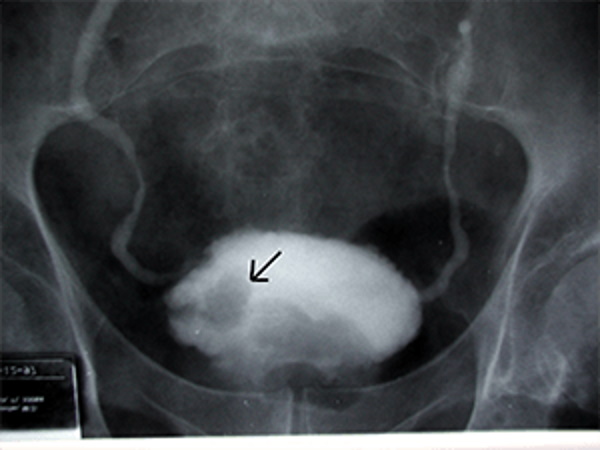

- Эндоскопия. Во время процедуры специалист визуально просматривает состояние мочевыделительной системы и определяет месторасположение полипа. В процессе цистоуретроскопии может быть произведен забор тканей для гистологии.

- Уретрография. Это один из наиболее современных методов диагностики полипов. В мочеиспускательный канал вводят рентгенконтраст – вещество в форме газа или раствора. Если пациентке сделают УЗИ, то на снимках специалисту будет видна локация доброкачественного новообразования, ее размер и степень сужения просвета.